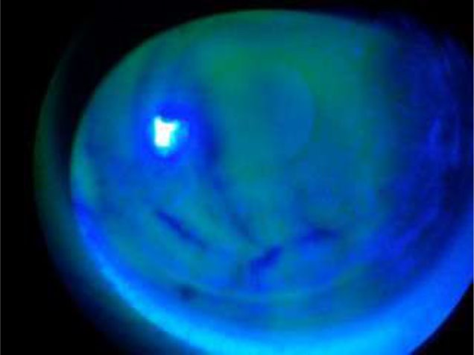

•Note the ‘green’ fluorescence indicating the area of ‘staining’

describe the different uses of sodium fl (4)

Detecting conjunctival and corneal lesions - corneal abrasion, dry eye disease, conjunctival follicles